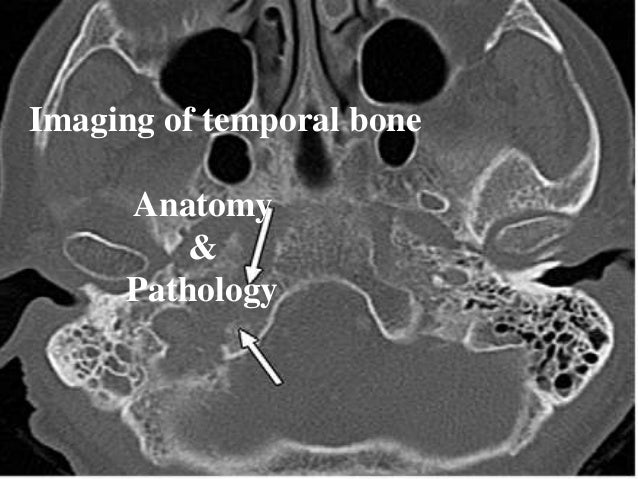

26+ Hrct Temporal Bone Test PNG. Learn vocabulary, terms and more with flashcards, games and other study tools. Compare cost and choose from high profile diagnostic test centers for all kind of ct scan and other the temporal bone is a pair of bones on the sides of the human skull which houses the middle and inner ear.

The open type cholesteatoma were much more common than the close type in our clinic. Temporal bone ct and mri anatomy harnsberger. Blithia was formed with the objective of simplifying diagnostics needs through convenience, information to compare and book a test, hassle free and professional diagnostic services at your doorstep.

Hrct examinations were performed on a 64 slice multidetector ct scanner.